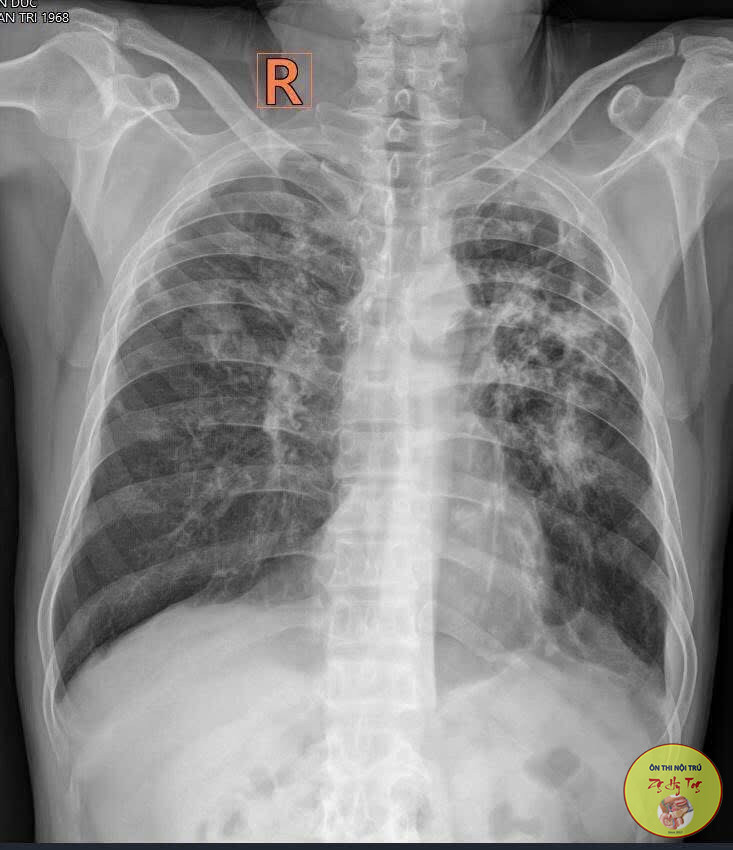

Ca lâm sàng thực tế, vận dụng lý thuyết bệnh học